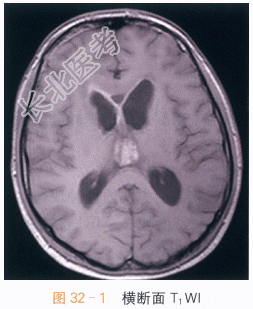

读片分析:头颅横断面T₁WI、T₂WI示松果体区不规则软组织肿块影,呈T₁WI等高、T₂WI低信号影,信号不均匀;横断面、矢状面T₁WI增强扫描可见病灶明显强化,室管膜亦可见明显强化。